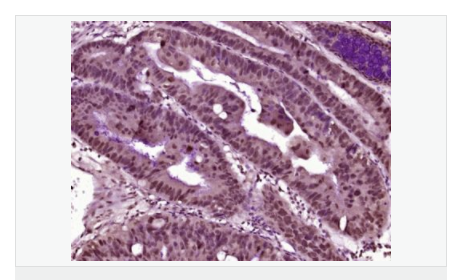

交叉反應:Human,Mouse(predicted:Rat,Dog,Pig,Cow,Horse,Rabbit) 推薦應用:IHC-F,IF,ELISA

| 產(chǎn)品應用 | ELISA=1:5000-10000 IHC-F=1:100-500 ICC=1:100-500 IF=1:100-500 (石蠟切片需做抗原修復) not yet tested in other applications. optimal dilutions/concentrations should be determined by the end user. |